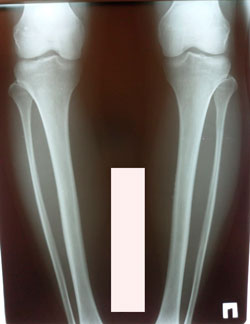

Исходник - 40 лет.

Дата операции - 25.01.2021

image-22-01-21-05-20-7.jpg

image-22-01-21-05-20-1.jpg